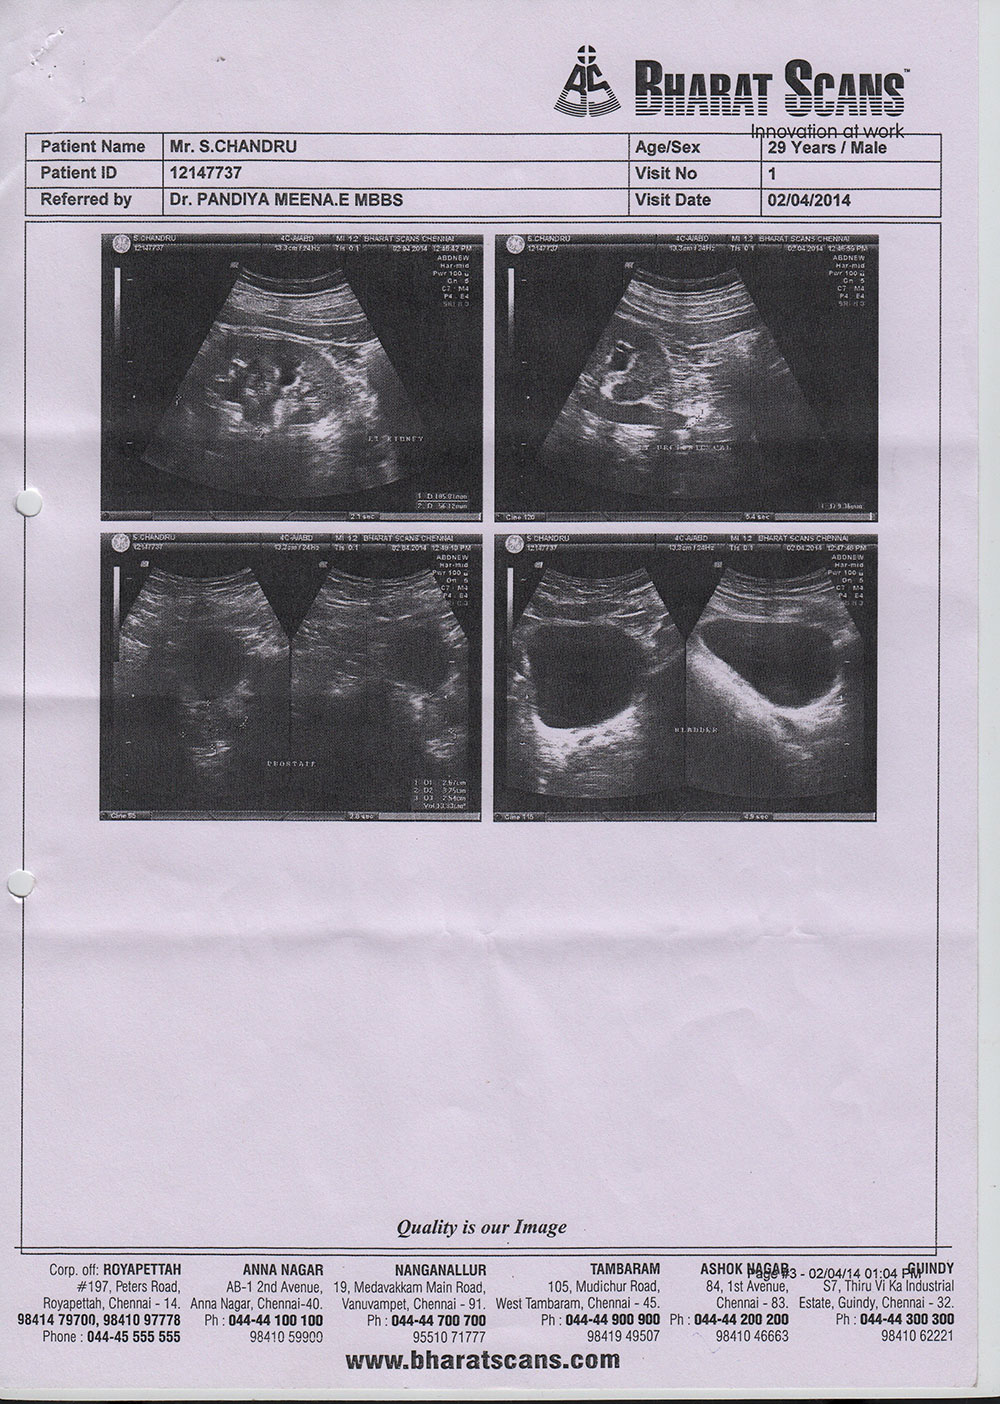

(Renal Calculi)“I was suffered with Kidney Stone problem since long time and it was repeating. On 02.04.2014 I registered myself and started treatment in HOMEOCARE INTERNATIONAL. Within 3months of the treatment it has controlled. On 13.07.2014, I have taken scan and the reports show that I have no Stones in Kidney. I am very thankful to Doctors at Homeocare International for treating me.”***